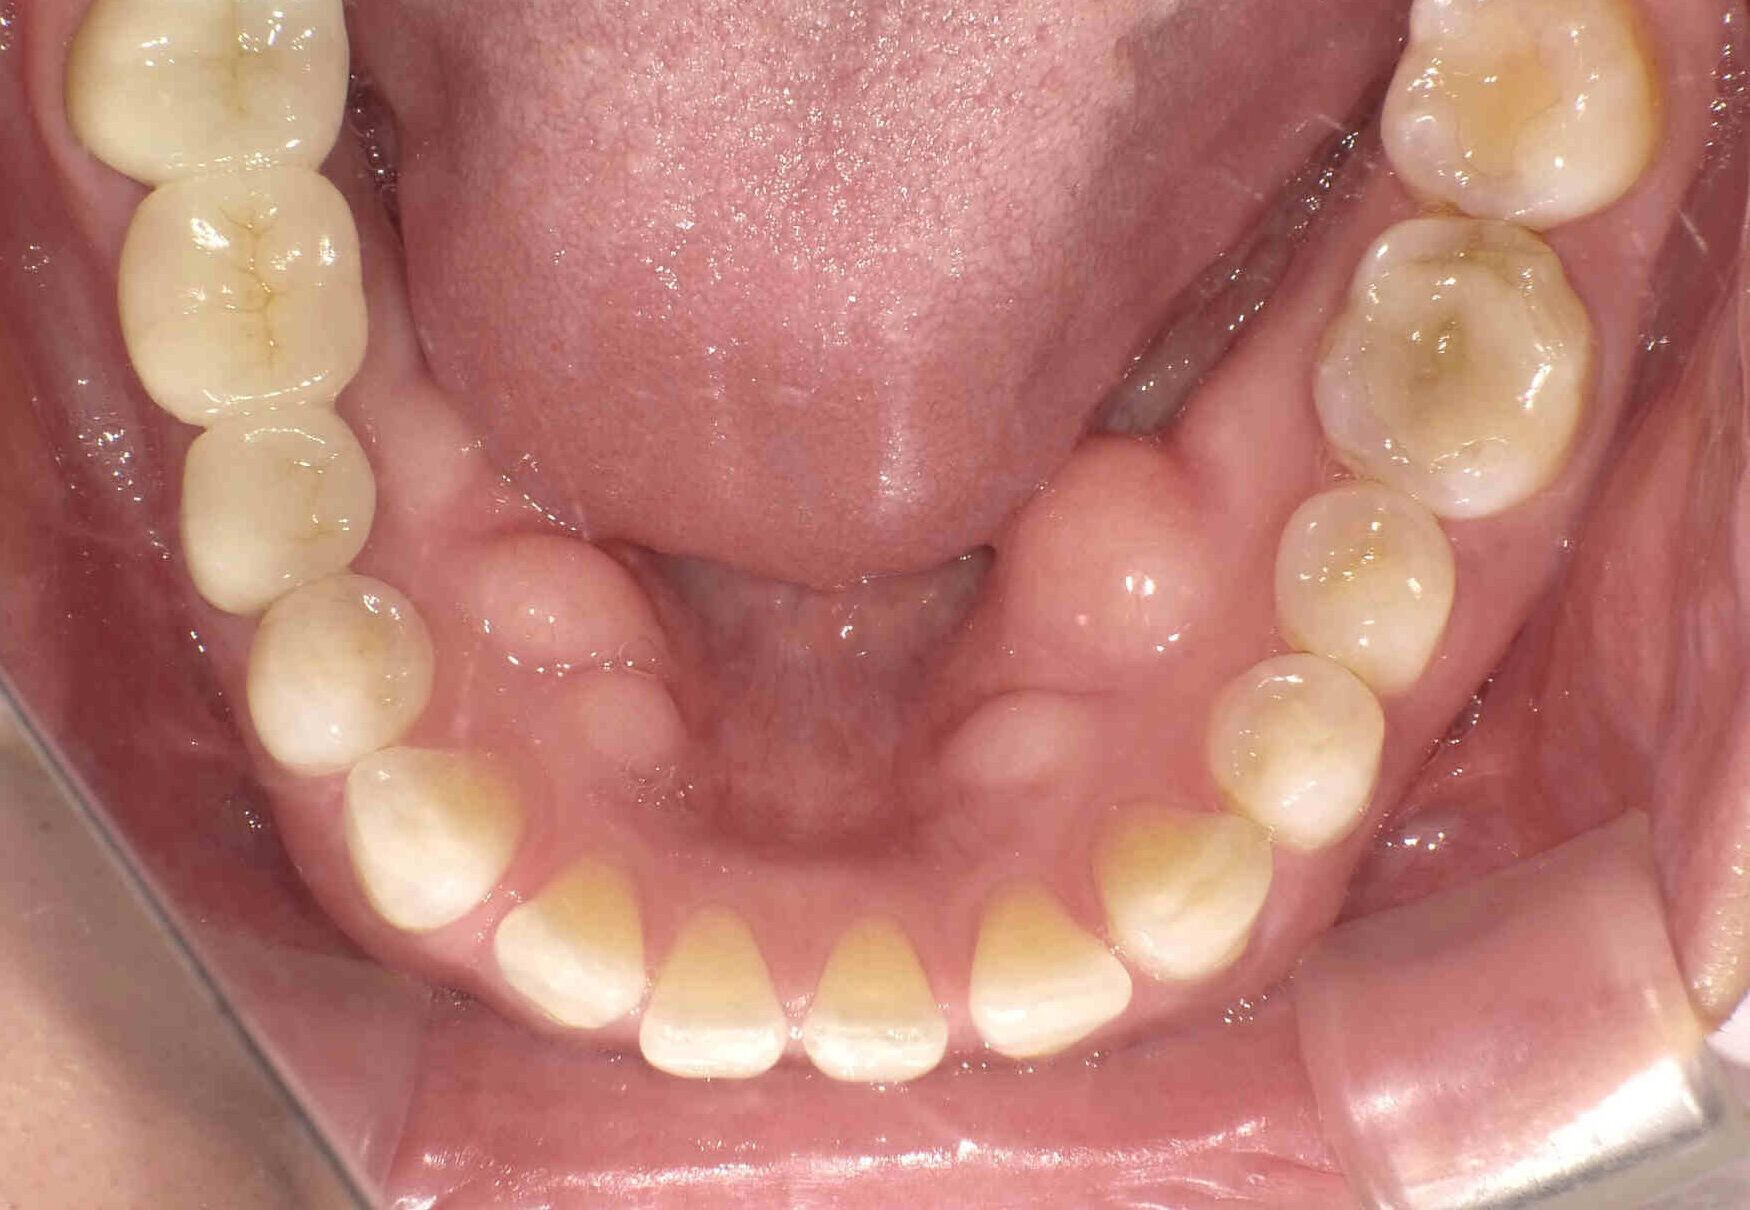

元々咬む筋力や食いしばり・歯ぎしりが非常に強く、『フレアーアウト』(前歯の歯並びが前方に放射状に倒れていく現象)によって「出っ歯」や「すきっ歯」の状態になっていました。

今回はご希望のマウスピース矯正で、食いしばりや歯ぎしりによる歯の破折やすり減りを予防しながら、歯と歯の隙間が広がって傾斜した前歯を元の位置に戻しました。

元々入っていた臼歯のブリッジは治療せず、そのままの位置で矯正を行うことを希望されたため、正中(上顎と下顎の中心線)を合わせることは難しいですが、美しい歯列と口元へ仕上がりました!